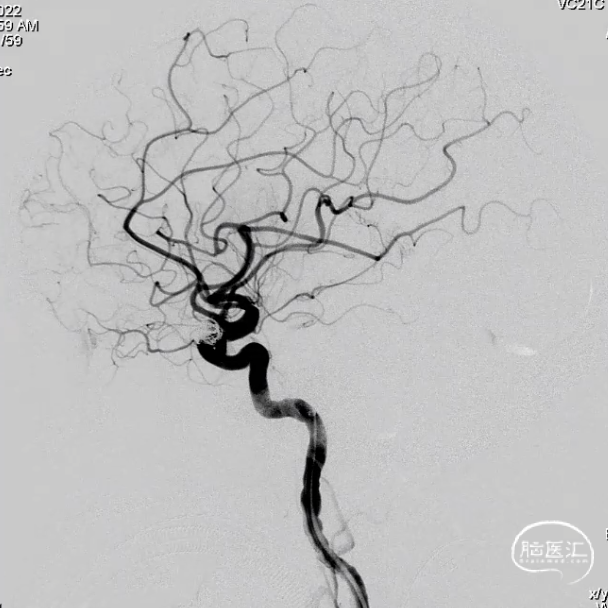

外院DSA

右侧颈内动脉眼动脉段-海绵窦段串联两枚动脉瘤,分别大小约:

① 8.8mm*5.9mm*5.2mm,瘤颈宽7.0mm;

② 6.8mm*4.3mm*3.6mm,瘤颈宽3.3mm。

左侧大脑中动脉分叉处微小动脉瘤大小约2.3mm*1.5mm*1.1mm,瘤颈宽1.7mm(不处理)。